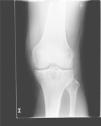

Laboratory tests showed uricemia of 9.4mg/dl and GGT 166U/dl. The remaining parameters (CBC, TSH, CPK, rheumatoid factor, HLA B27, anti-CCP antibodies, immunoglobulins, 24h urine uric acid) were normal. X-rays of the left foot were performed (Fig. 1), showing marginal erosions and sclerotic borders of the first metatarsal head, with increased adjacent soft tissue. A left knee radiograph (Fig. 2) showed lytic lesions with well-defined edges and incipient degenerative changes of the tibial epiphysis at the femorotibial level. We performed arthrocentesis of the left knee. Monosodium urate crystals were found in synovial fluid (SF). SF culture was negative.